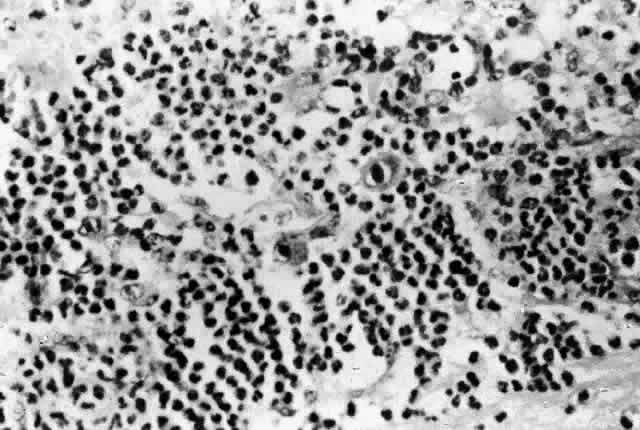

In cases with full-thickness necrosis, the retina appears to have a thick, densely opaque appearance with sharply demarcated borders. There is usually little hemorrhage. There may be inflammatory vascular sheathing, but this sign is not helpful in differentiating ocular toxoplasmosis from other infections, such as CMV retinopathy or syphilis. A prominent inflammatory reaction in the vitreous and anterior chamber has been described by some investigators, while others report little associated vitritis or iridocyclitis.50,51 Histopathologic examination of lesions reveals both trophozoites and cysts in areas of retinal necrosis and within retinal pigment epithelium (RPE) cells (Fig. 5).48 Organisms can be found in fewer numbers in the choroid and vitreous. The optic nerve may also be infected.48,51,52 Although a prominent choroidal inflammatory reaction may be present, there is usually scant inflammatory material in the necrotic retina.48,51

Fig. 5. A prominent Toxoplasma gondii cyst in necrotic retina of a patient with AIDS and ocular toxoplasmosis (arrow). There is little tissue inflammation (hematoxylin-eosin, original magnification [A5];times; 600). (Photograph courtesy of Ben J. Glasgow, MD)